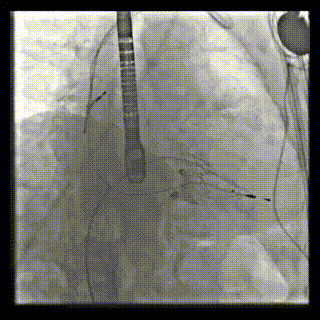

本周三例接受LuX-Valve Plus經血管三尖瓣置換術的患者中,第一例患者為冠狀動脈旁路移植術+Bentall+二尖瓣成形術后;第二例患者為永久起搏器植入術后,存在跨三尖瓣導線;第三例患者合并房顫、房缺及左心耳封堵術后。

三例患者入院后,葛均波院士團隊周達新教授、潘文志教授、張源博士、陳莎莎博士及心超室的潘翠珍教授、李偉教授對患者的情況進行詳細評估和討論,最終決定為三例患者選擇LuX-Valve Plus40mm、50mm和50mm型號的瓣膜進行手術治療。手術后即刻拔除氣管插管,術后患者三尖瓣反流癥狀得到顯著改善,復查心超結果顯示人工三尖瓣瓣膜支架固定穩定,瓣葉關閉形態未見異常,未見明顯反流。